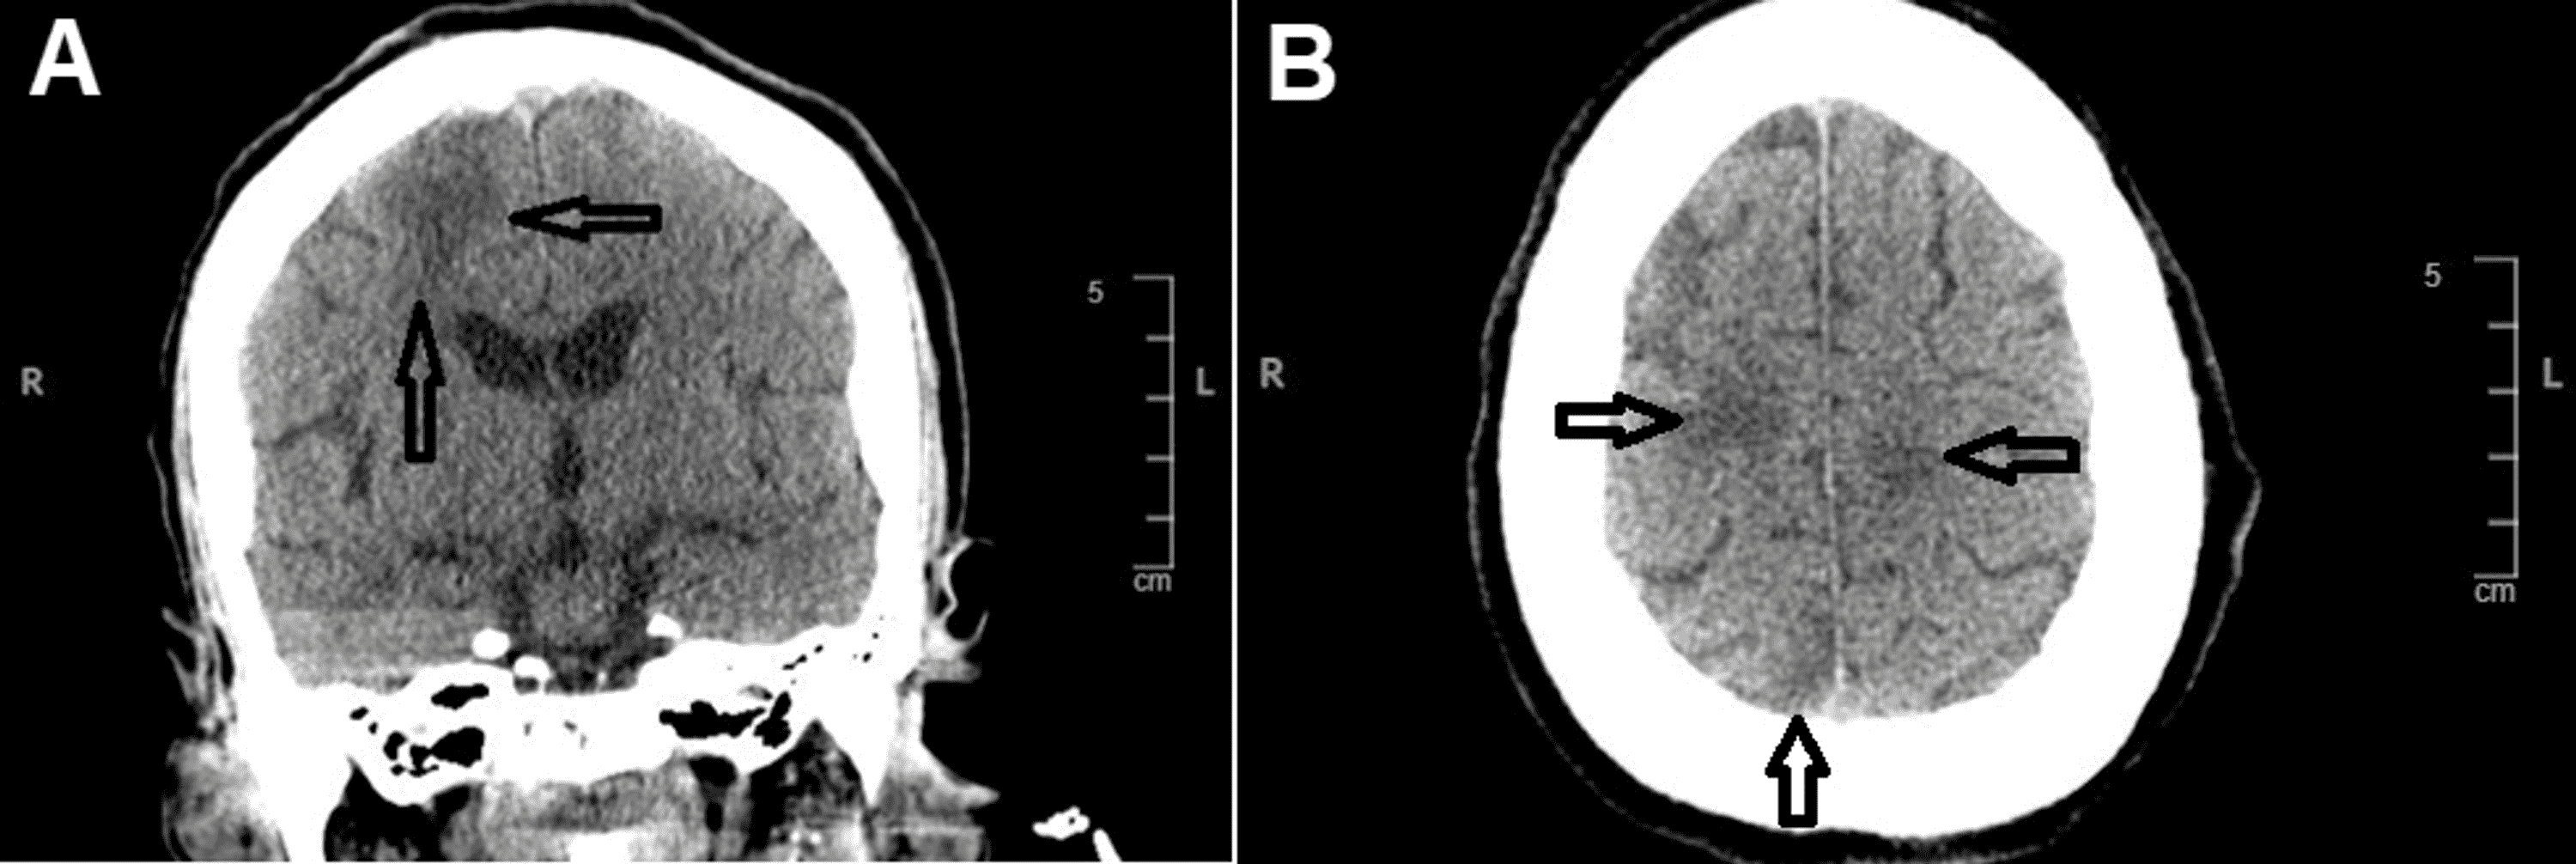

Shrinking central nervous system in systemic lupus erythematosus Lupus And Brain Patients with systemic lupus erythematosus (sle) frequently show symptoms of central nervous system (cns) involvement,. White matter lesions and brain atrophy in systemic lupus erythematosus patients: When lupus affects the brain and spinal cord, it’s called neuropsychiatric lupus, lupus cerebritis, or central nervous system (cns) lupus. Correlation to cognitive dysfunction in a cohort. When it affects the brain, spinal cord. Lupus And Brain.

Cureus Lupus Cerebritis as a Rare Neuropsychiatric Manifestation of Lupus And Brain Learn how lupus can affect the brain and other parts of the nervous system, and what symptoms and treatments to expect. Learn how lupus can affect the brain and spinal cord, causing cognitive dysfunction, headache, fibromyalgia, and other conditions. When it affects the brain, spinal cord or nerves, it is called neuropsychiatric lupus and can cause a tangled web of. Lupus And Brain.